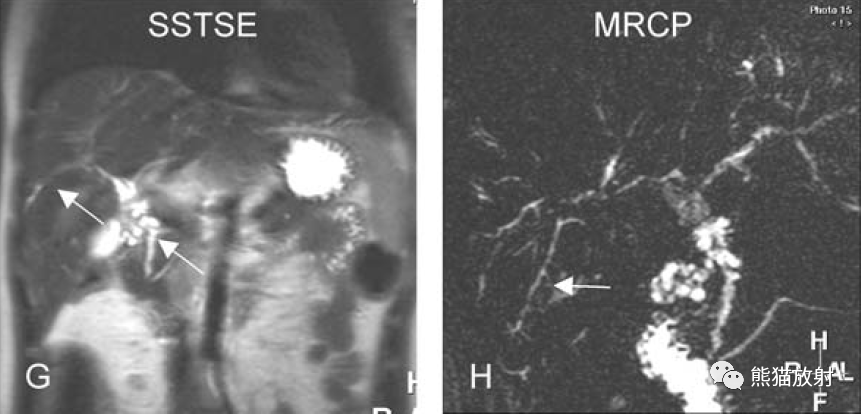

PSC A~D图:表现如上所述。E图:T2WI-FS上扩张胆管与周围高信号血管不易区分;F图:T2WI上扩张的肝内胆管可延续至肝被膜下;G、H图:MRCP示PSC典型表现,胆囊增大提示排空受阻,胆总管狭窄所致。

PSC。A~D图:表现如上所述。E~G图:肝内和肝外胆管异常(箭头)提示全身性疾病。H图:MRCP显示典型PSC的胆系表现,细长的肝内胆管,走行僵直,延伸至肝被膜下(箭头),肝外胆管粗细不均,管壁毛糙。